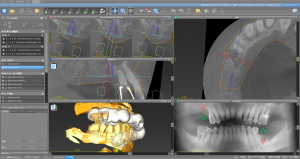

デジタルシュミレーションソフト上で自分の骨に安全・正確にインプラントを埋入できるサージカルガイドを作成し(ガイドサージェリー)、

歯茎をめくらず最小限の傷口で(フラップレス手術)インプラント治療を行いました。(右上・左下に1本ずつ)

安全に、そしてシュミレーション通り正確に、短時間で手術は終了したため、患者様は疲れもなく、術後の腫れや痛みもほとんど無かったとおっしゃっていただきました。

これもまた、口腔内スキャナーにてスキャンした口腔内デジタル画像(従来でいうところの歯型取り)からのデジタルデータで作製した高精度のインプラント技工物(チタンアバットメント&フルジルコニアクラウン)を先日、装着いたしました。

一昔前は身体に大きな負担を強いて行わなければ実現できなかったであろう治療をデジタルソリューションを駆使することで、旧来に比べ安全・正確に、治療期間・費用を抑えて治療を実現できました。